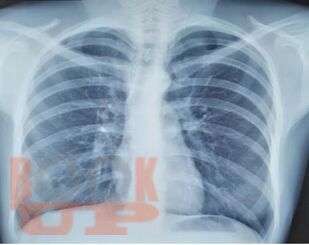

Учебное пособие составлено в соответствии с требованиями ФГОС ВО по специальностям 31.05.01 Лечебное дело и 31.05.02 Педиатрия, рабочей программы дисциплины «Фтизиатрия» (2018). В пособии собраны воедино и обобщены сведения о лучевой диагностике туберкулеза органов дыхания, включена клиническая классификация туберкулеза, иллюстрированная рентгенограммами больных, лечившихся в КГБУЗ «Красноярском краевом противотуберкулезном диспансере №1» с 1980-х г. по настоящее время.